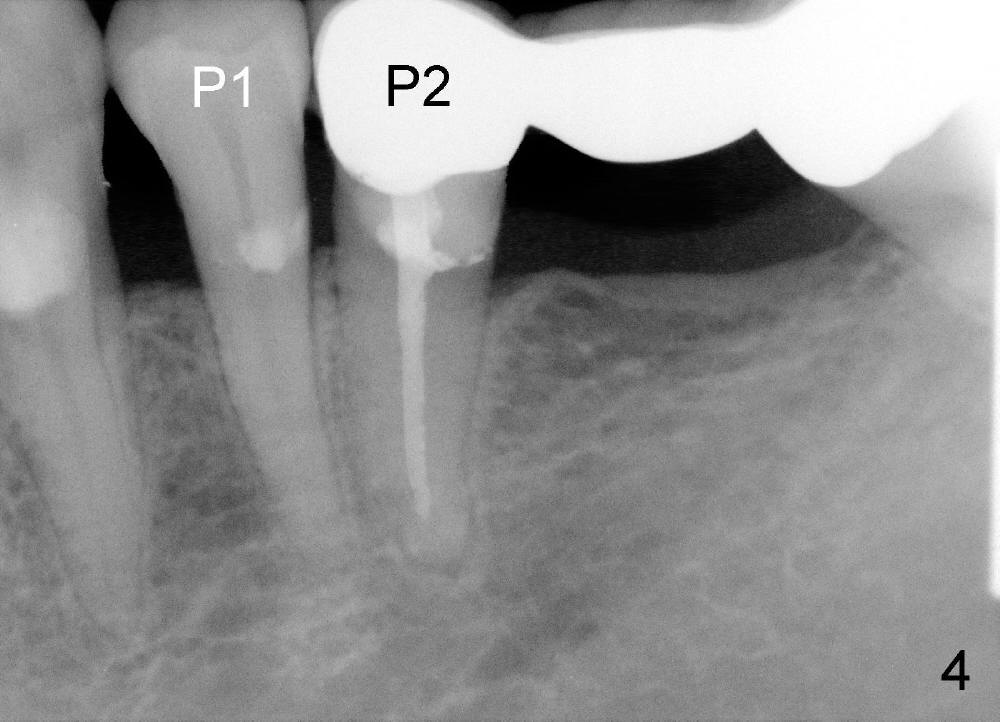

比较上文图一图二,我们可以发现第二前磨牙牙冠下面所谓裂纹(上文图二白箭头)似乎五年前也可以看见(上文图一)。当病人第二次回诊所,我们再次仔细检查发现那个牙齿(本文图一P2)的确有牙颈部缺损(黑箭头),仿佛牙髓暴露(白箭头)。当从牙冠牙合面开髓(其实这项手术很危险,容易穿髓),插入十号牙髓针(图二F),牙髓针的下部在牙颈部缺损暴露(^,不巧当时橡皮障掉下来)。第一前臼齿有一牙颈部树脂修复(C)以及继发性龋齿(<)。总之第二双尖牙牙髓炎很可能由于牙颈部缺损穿髓造成,根管治疗会解决疼痛问题,至于根管治疗后牙齿可能断裂是以后问题。